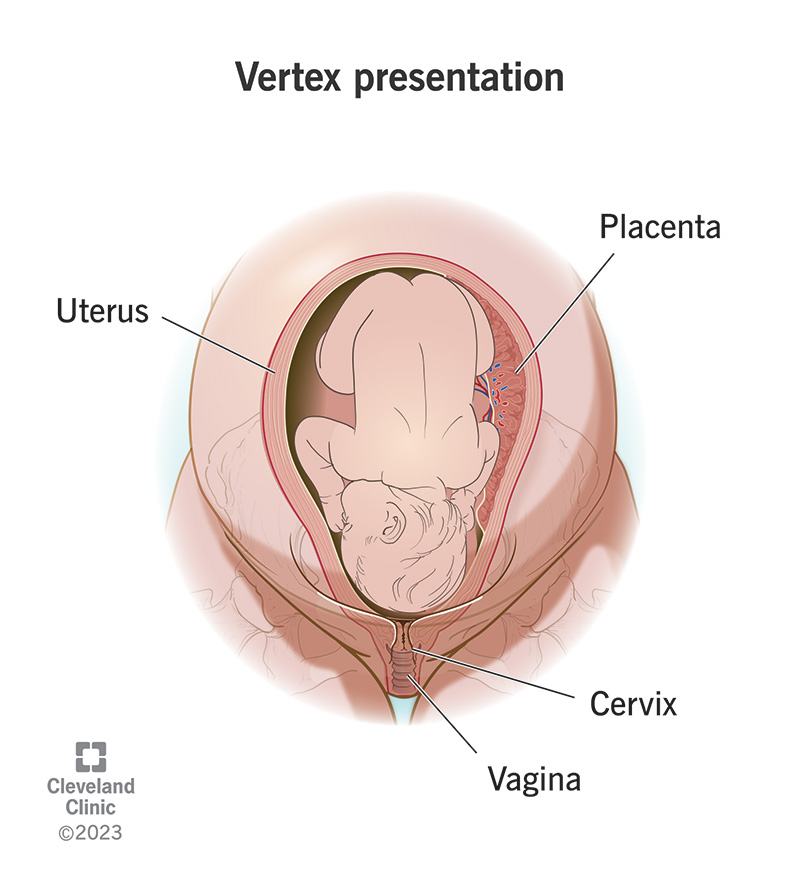

Most babies turn into a vertex (head down) presentation during this month.

X. End of 40th Gestational Week (Third Trimester)

Length: 48–52 cm (crown to rump, 35–37 cm)

Weight: 3000 g (7–7.5 lb)

The fetus

kicks actively, hard enough to cause the mother considerable discomfort.

Fetal hemoglobin begins its conversion to adult hemoglobin. The conversion is so rapid that, at birth, about 20% of hemoglobin will be adult in character.

Vernix caseosa is fully formed.

Fingernails extend over the fingertips.

Creases on the soles of the feet cover at least two-thirds of the surface